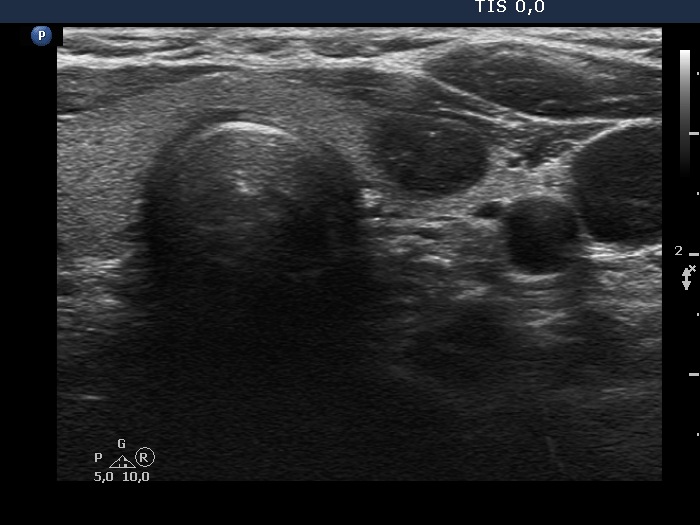

Five months after the first examination (third row of images)

Clinical presentation: The patient had no complaints. She was referred for evaluation of an elevated TSH level.

Palpation: no abnormality.

Laboratory tests: 4.76 mIU/L, aTPO 0,6 U/mL.

Ultrasonography. The thyroid was echonormal. There was a hypoechoic nodule in the ventral part of the left lobe. The ventral borders of the lesion were undefined because the echogenicity of the lesion and the neighboring strap muscle was identical.Suggestion: TSH in a year, ultrasound in two years, in the event of complaints at once.

- Compared with the nodule just after the aspiration with that seen five months later, a spontaneous further decrease can be observed.

- On the second examination, we cannot see cystic portions, therefore the intranodular echogenic figures might cause concern. However, if we take the ultrasound pattern at the previous examination into account, this concern is not justified.

- The presentation of the nodule at the follow-up is an example of non-pathological cause of blur.